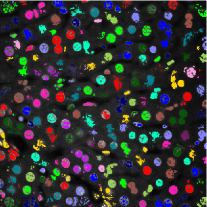

Figure 3 shows the synthetic images generated by our proposed method. The left column indicates original images whereas middle column shows synthetic images artificially generated from corresponding synthetic binary images provided in right column. As can be seen from Figure 3, the synthetic images reflect characteristics of the original microscopy images such as background noise, nuclei shape, orientation and intensity.

To make this clear, segmentation results were color coded using 3D connected component labeling and overlaid on the original volumes. The method from [20] cannot distinguish between nuclei and non-nuclei structures including noise. This is especially recognizable from segmentation results of Data-I in which multiple nuclei and non-nuclei structures are colored with the same color. As can be observed from Figure 6 and 6, segmentation masks are smaller than nuclei size and suffered from location shifts. Conversely, our proposed method shown in Figure 6 and 6 segments nuclei with the right shape at the correct locations.